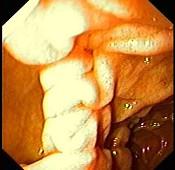

女性,45岁。腹部饱胀不适2年余。表情自然,皮肤无黄染,未见蜘蛛痣,巩膜无黄染。腹平坦,腹肌软,全腹无压痛反跳痛,肝脾肋缘下0.5cm,胃镜检查如下图,诊...

问题 女性,45岁。腹部饱胀不适2年余。表情自然,皮肤无黄染,未见蜘蛛痣,巩膜无黄染。腹平坦,腹肌软,全腹无压痛反跳痛,肝脾肋缘下0.5cm,胃镜检查如下图,诊断为 ( )

选项 A.十二指肠憩室 B.十二指肠溃疡 C.十二指肠炎 D.十二指肠穿孔 E.十二指肠雍滞症

答案 A